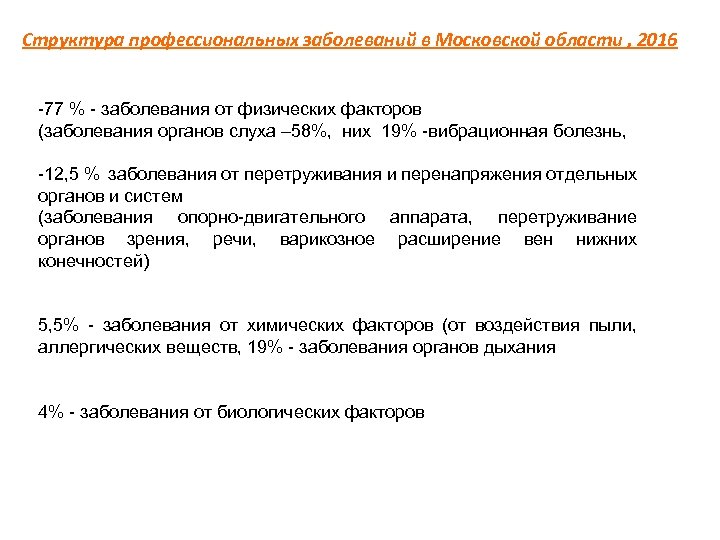

Структура профессиональных заболеваний в Московской области , 2016 77 % заболевания от физических факторов (заболевания органов слуха – 58%, них 19% вибрационная болезнь, 12, 5 % заболевания от перетруживания и перенапряжения отдельных органов и систем (заболевания опорно двигательного аппарата, перетруживание органов зрения, речи, варикозное расширение вен нижних конечностей) 5, 5% заболевания от химических факторов (от воздействия пыли, аллергических веществ, 19% заболевания органов дыхания 4% заболевания от биологических факторов

Структура профессиональных заболеваний в Московской области , 2016 77 % заболевания от физических факторов (заболевания органов слуха – 58%, них 19% вибрационная болезнь, 12, 5 % заболевания от перетруживания и перенапряжения отдельных органов и систем (заболевания опорно двигательного аппарата, перетруживание органов зрения, речи, варикозное расширение вен нижних конечностей) 5, 5% заболевания от химических факторов (от воздействия пыли, аллергических веществ, 19% заболевания органов дыхания 4% заболевания от биологических факторов